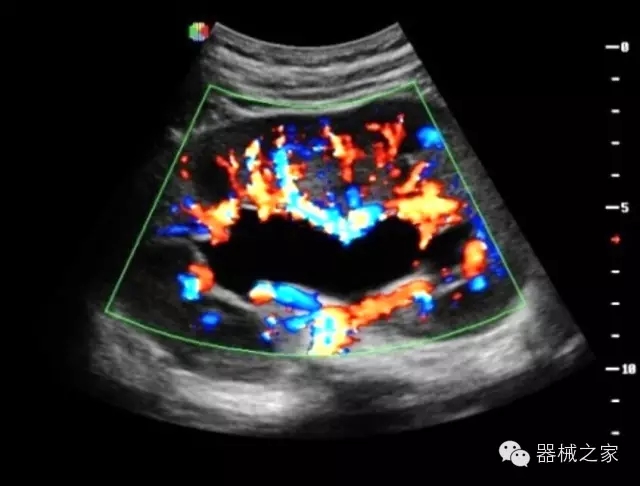

臨床圖片賞析

·全球目前唯一一款配備主機(jī)雙探頭接口,整機(jī)重量(含電池)在5公斤以內(nèi)的便攜式彩超;

·獨(dú)有的HoloTM PW 實(shí)時(shí)3取樣門(mén)PW成像技術(shù),精確進(jìn)行血管診斷;

·一鍵優(yōu)化B、Color、PW,Auto Doppler自動(dòng)識(shí)別血管位置、偏轉(zhuǎn)角度等,提高工作效率;